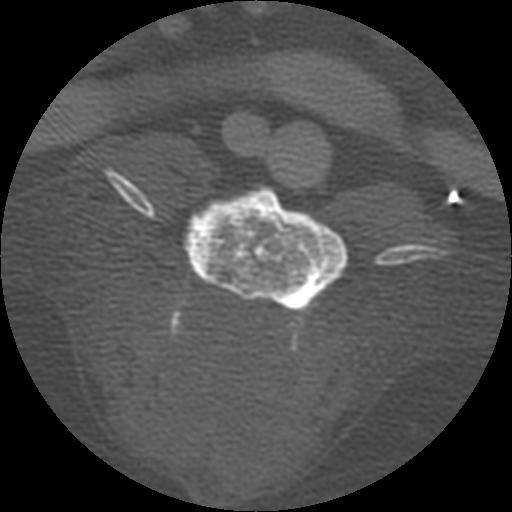

This week’s case is a 14-year-old female neutered Golden Retriever with progressive paresis of both hind limbs.

On the lateral radiograph, a large osteolytic site is present at the caudal aspect of the lamina of L4. This results in loss of the caudal half of the lamina and the articular facets of L4 with loss of the pedicles evident on the ventrodorsal projection. There is dural ossification in the cord. There is extensive ventral spondylosis throughout the lumbar vertebral column. No other sites of osteolysis are identified.

On the 1 mm, post contrast CT images, there is extensive osteolysis in L3 and L4 involving the vertebral bodies, laminae and dorsal spinous processes. There is a non contrast-enhancing soft tissue mass dorsal to the vertebrae.